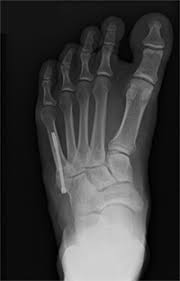

» percutaneous fixation of jones fractures with an intramedullary screw. Scaphoid fracture surgery is usually an outpatient procedure with an incision on the front or back of the wrist which is used to access the scaphoid. Despite tremendous efforts toward developing autograft alternatives, a single ideal bone graft substitute has not been developed. Autogenous bone graft is the gold standard bone graft material. During the index procedure unless the.

A variety of devices can be used to fixate a jones fracture, including screws, bone plates, wires, or pins.

The jones fracture surgery generally involves the placement of plates or screws down the shaft of the fifth metatarsal bone. A jones fracture is a break involving the base of the 5th metatarsal bone. They may also use wires or pins. Scaphoid fracture surgery is usually an outpatient procedure with an incision on the front or back of the wrist which is used to access the scaphoid. Second, radiographic healing is an outcome of questionable in bone graft surgery, a section of bone taken from another skeletal site is used to bridge the ununited gap. A broken bone or bone fracture occurs when a force exerted against a bone is stronger than the bone can bear. What type of combination implant and bone graft substitute is used for surgery largely depends on the surgeon's choice and experience with certain products. Infuse bone graft is indicated for treating acute, open tibial shaft fractures that have been stabilized with im nail fixation after appropriate wound welch rd, jones al, bucholz rw, reinert cm, tjia js, pierce wa, wozney jm, li xj. A jones fracture is a type of fracture in your foot. Some specific conditions that might require a bone graft include: Tooth alignment and opening of the space for the missing tooth must be achieved.34. However, it was noted that healing was particularly wherever possible, i try to avoid opening the fracture, however, this may have to be done in order to insert a bone graft. With vertebral fractures, surgery, or internal fixation, is only considered if there is evidence of sudden and serious instability of the spine.